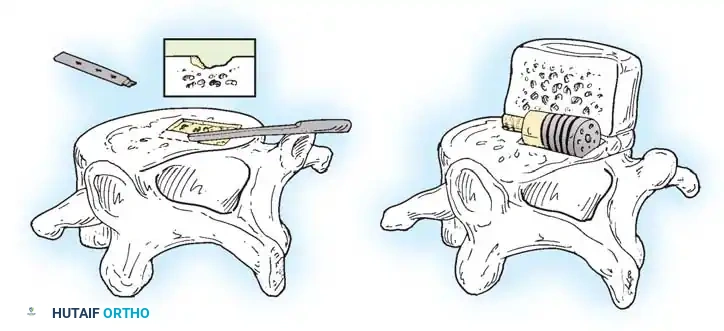

- Discectomy and Endplate Preparation: A thorough annulotomy is performed. The disc material is evacuated using pituitary rongeurs and curettes. The cartilaginous endplates are scraped to expose bleeding subchondral bone, ensuring a robust fusion bed.

- Cage Insertion: An interbody cage, packed with bone graft, is impacted into the disc space. This maneuver restores foraminal height and tension on the annulus, often achieving partial reduction of the slip.